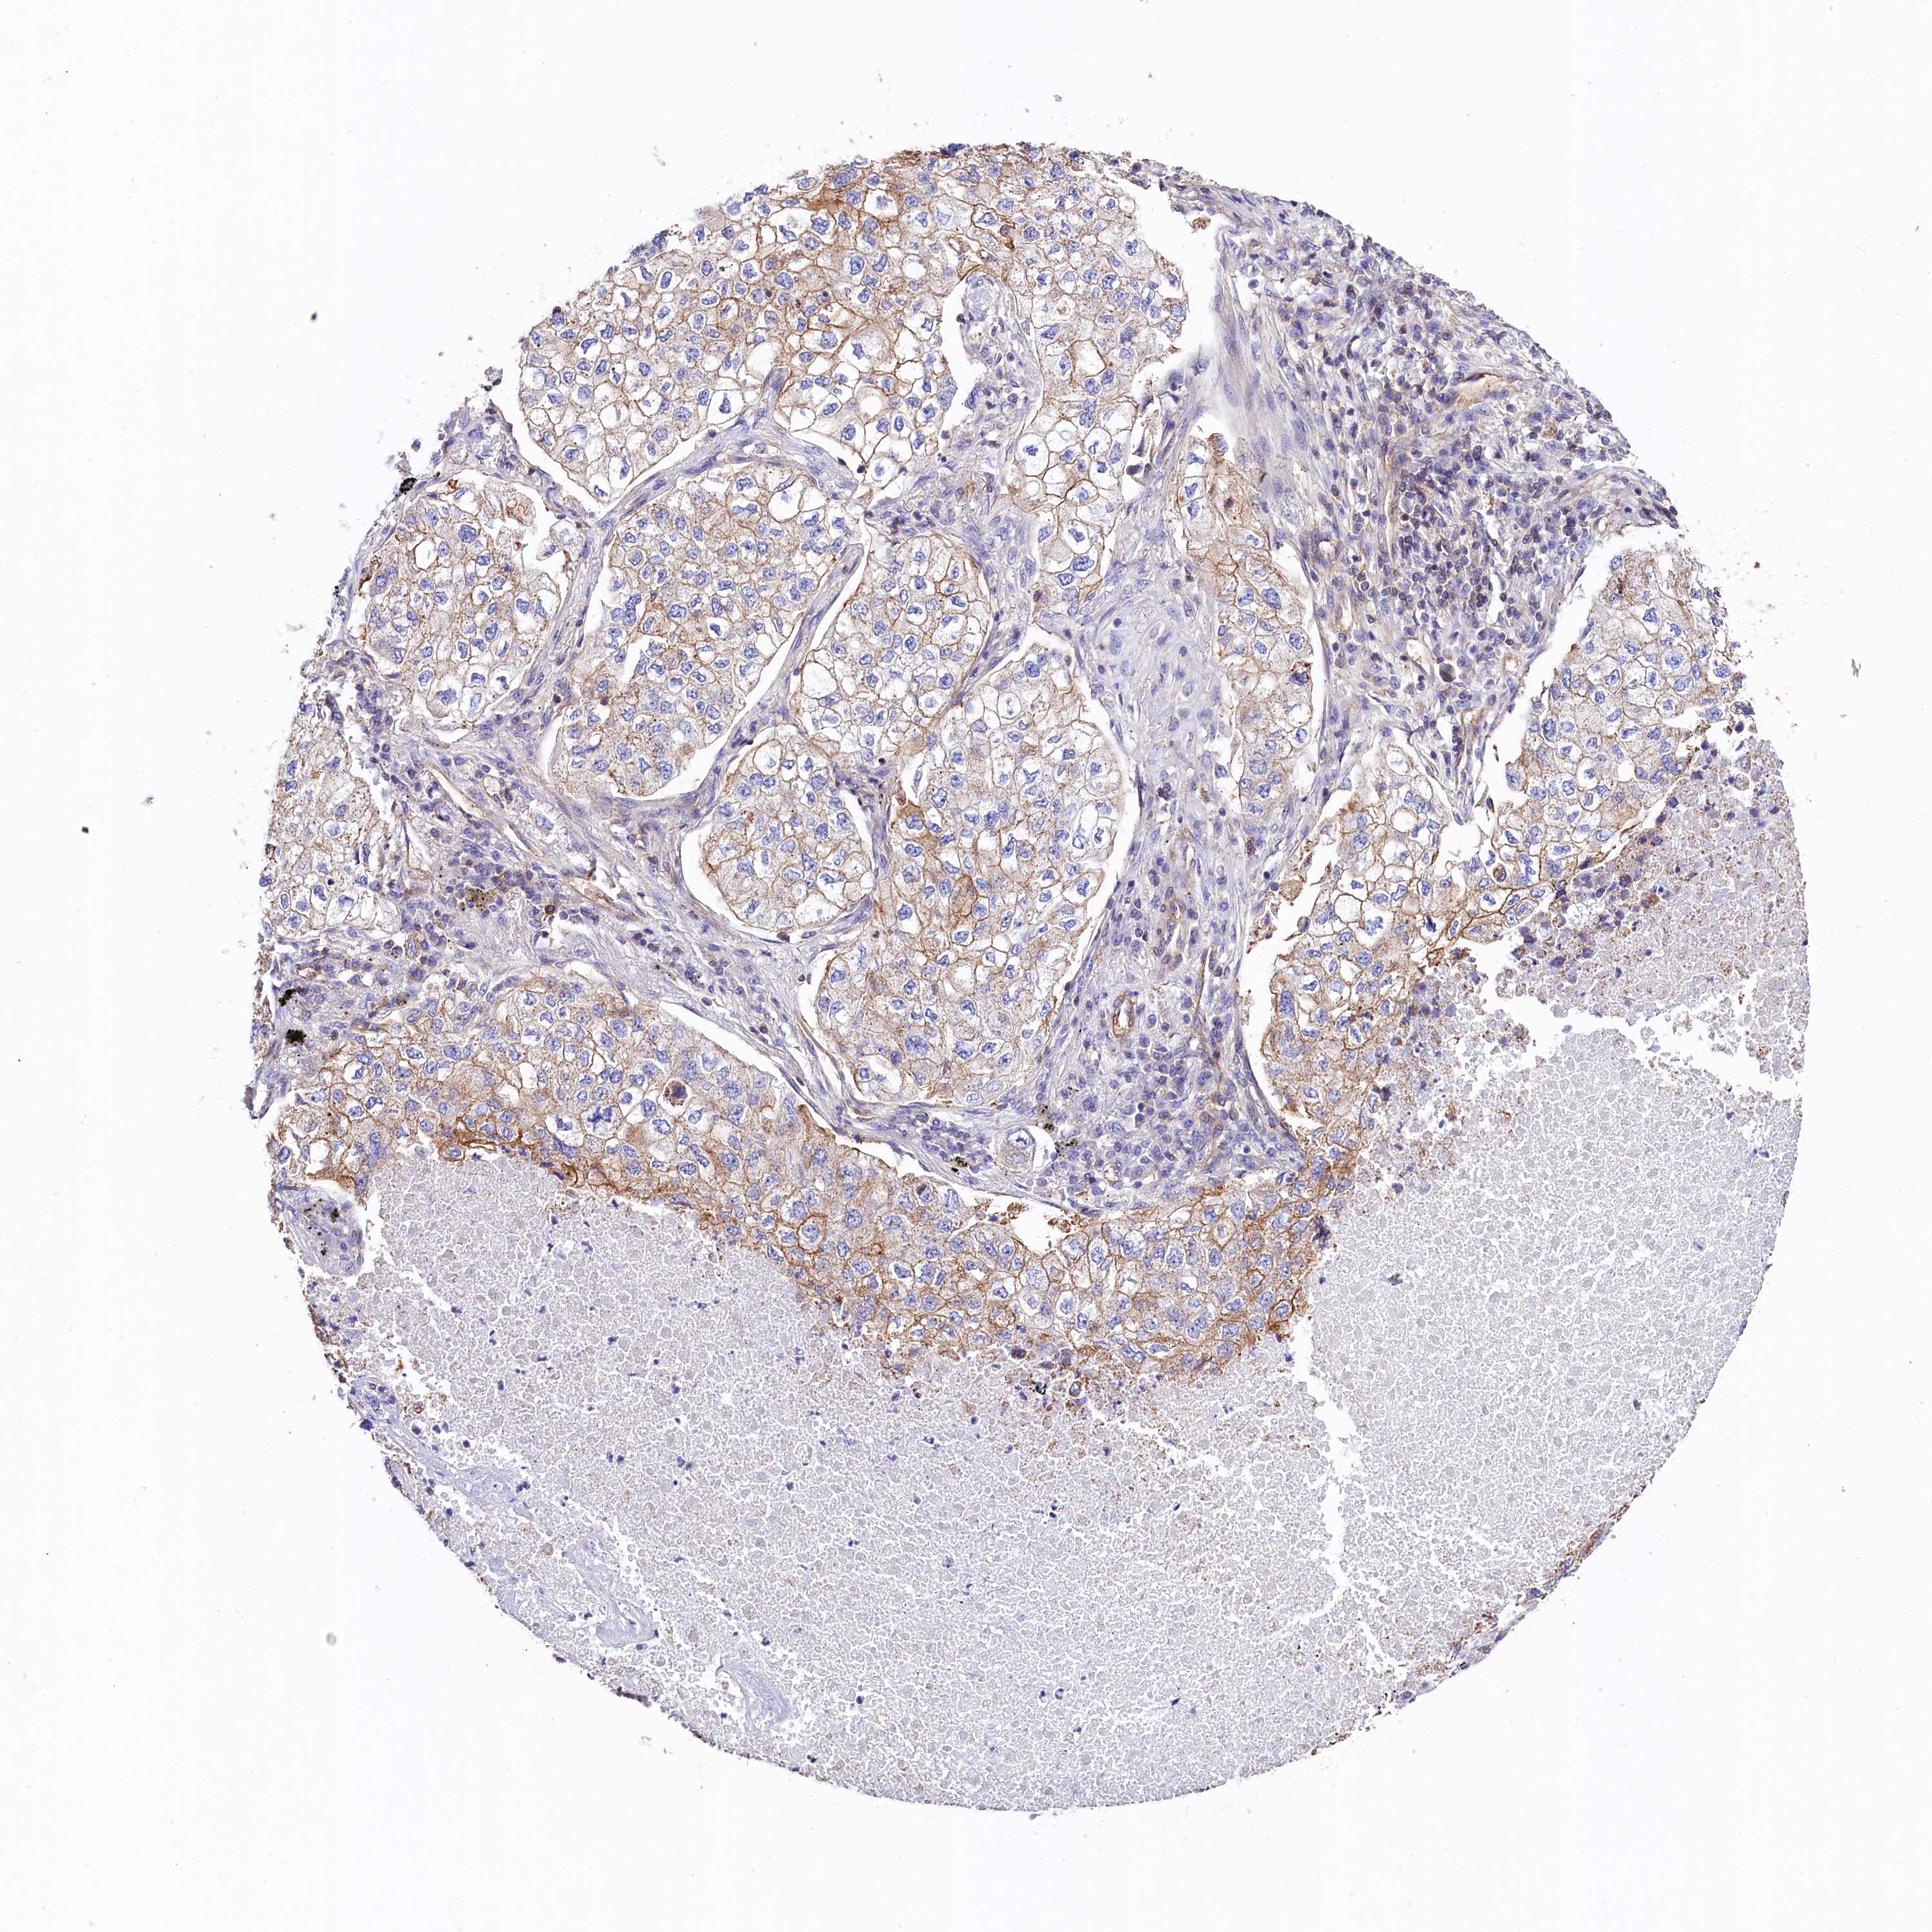

ATP2B4